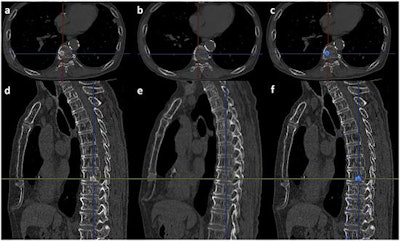

- Finally, the color-coded difference of the 3D model is superimposed on the follow-up monochromatic MPR images. Osteolytic lesions (blue) and osteoblastic lesions (red) are color-coded. The case below shows vertebral metastases diagnosed by the CAD software.

A case of osteoblastic metastasis in the body of the ninth thoracic vertebra. (a) Follow-up axial image. (b) Initial axial image. (c) Result of the 3D CT subtraction. The blue color indicates the metastasis. (d) Follow-up sagittal image. (e) Initial sagittal image. (f) Result of the 3D CT subtraction. The blue color indicates the metastasis. Image republished courtesy of PLOS One, January 17, 2016.Improvement for all readers, lesion types